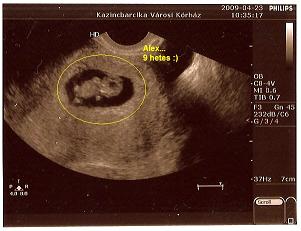

Nem tudni, hogy fiú-e vagy lány.Bár anyósom a laikus, már megállapította ebből a képből, hogy fiú.

Alex... a neve mert vagy Alexander vagy Alexandra lesz.

A fiúnak keményebb az , hogy Orbán Alexander minthogy Orbán Alex, a lány meg amúgy is tecc és szempont az is, hogy mindkettő össze-vissza becézhető és külföldön is ismert (ki tudja mit hoz a jövő?).